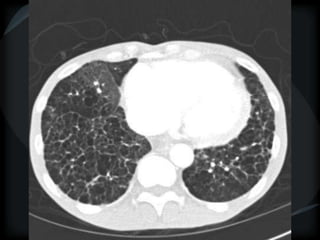

RETICULAR PATTERN - UIP

 peripheral reticular lines / inter and intralobular septae

 honeycomb

 Traction bronchiectasis

 None or minimal ground glass

 Gradient increasing from apex to base

 Skip areas

 Chronic HP = upper and midzones

Chronic HP